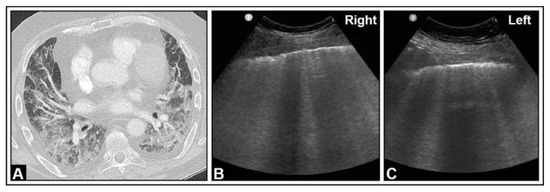

5. Pneumonia